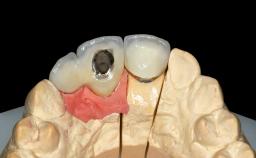

Replacement of Two Central Incisors and One Lateral Incisor with a Fixed Dental Prosthesis on Two Bone-Level Implants

A 38-year-old woman presented with an esthetically unacceptable fixed partial denture replacing teeth 11, 21, 22. She had lost these teeth due to trauma when she was a child. The patient was not in pain but very concerned based on her previous experience that dental treatments had never satisfied her esthetic expectations. She was in good general health and reported no regular medications. No periodontal disease was noted despite the fact that the buccal flange of the prosthesis impeded cleaning of the tooth abutments. The patient did not smoke and complied with home maintenance requirements, as evidenced by her good oral hygiene status.

# of Implants | 2 |